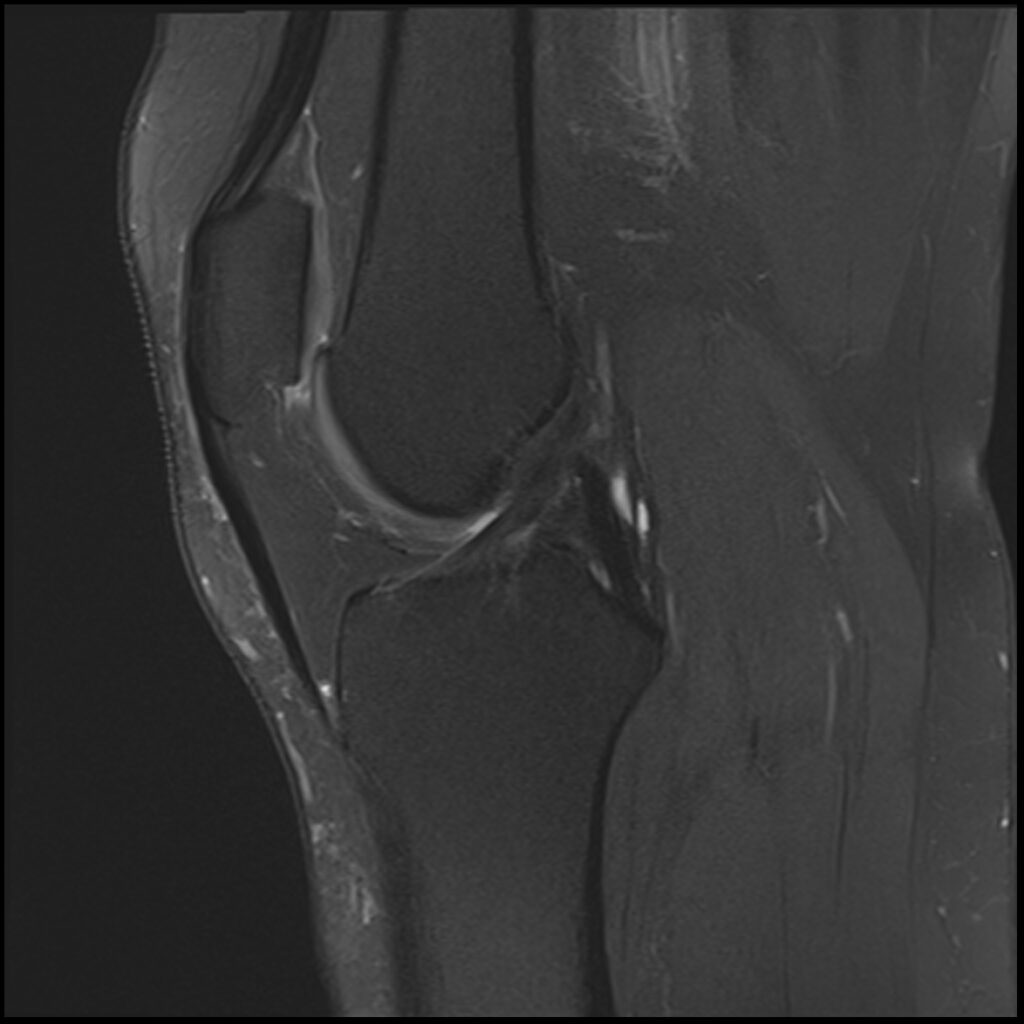

Patient D, age 19, sustained a competitive tumbling injury that involved a hard landing with the pathognomonic plant and pivot that directly tractions the ACL along its doubly obliqued path. The first MR scan was done the day after the trauma. She was initially treated 5 days post-injury. Her knee effusion was completely aspirated, then replaced with 3cc of autologous platelet-rich plasma and 5cc of platelet-poor plasma. Using ultrasound guidance, the ACL origin at the posterior femur was treated after carefully avoiding the vasculature and nerves. She was then instructed not to bear weight for 3 days, then use crutches/assisted weight bearing for 2 weeks. She was then to use a compression knee sleeve during sports or exercise. At her follow-up visit at 4 weeks, she was still having some instability at times and lateral knee pain. Her knee was evaluated with an ultrasound, and any areas of pathology seen were treated with hypertonic dextrose injection and needling technique. This included her medial and lateral collateral ligaments, and the patellar tendon and ligament. At 12-week follow-up, she continued to have some minor issues with her knee, so another evaluation and treatment were performed with hypertonic dextrose to the injured ligament and tendon areas found on the ultrasound examination. We obtained a new MR for her 16-week follow-up and noticed the ACL had re-ligamentized, and she reported full function and return to exercise. At 5-year follow-up, she claimed she was fully active, pain-free, but no longer tumbling.

Patient D Before

Patient D After